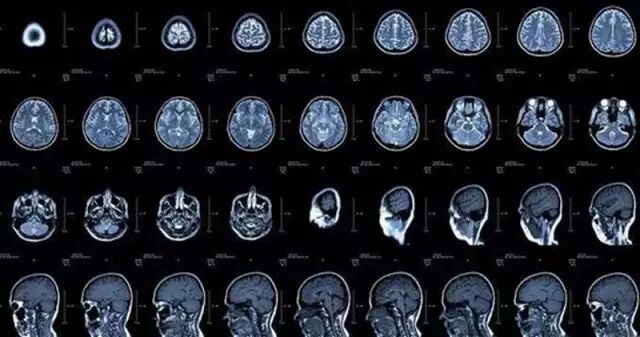

CT

CT的检查原理是X线分层穿过人体,之后通过电脑计算后二次成像,如同把一个西瓜连续切成片来看,片越薄片数越多,当然看得越仔细。

MR

磁共振也叫MR,是采用磁场原理计算成像,由于不是采用X线成像,避免了X线对人体的不良影响。温馨提示,到MR检查间一定不要携带铁磁性物品,不然被机器吸过去,你要惹大麻烦的。